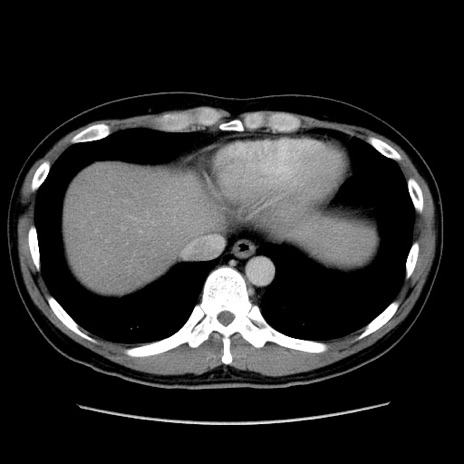

症例4(横断像)

【症例】30歳代男性

【主訴】腹痛、嘔吐

【現病歴】昨晩から突然の腹痛あり、その後嘔吐、軟便も出現。腹痛が改善しないため救急搬送となる。2日前にしめ鯖の食事歴あり。

【身体所見】意識清明、苦悶様、BP 135/90mmHg、BT 35.7℃、腹部:平坦、やや硬、心窩部〜臍部に自発痛、圧痛あり、筋性防御+、反跳痛-

【データ】WBC 8100、CRP 0.57